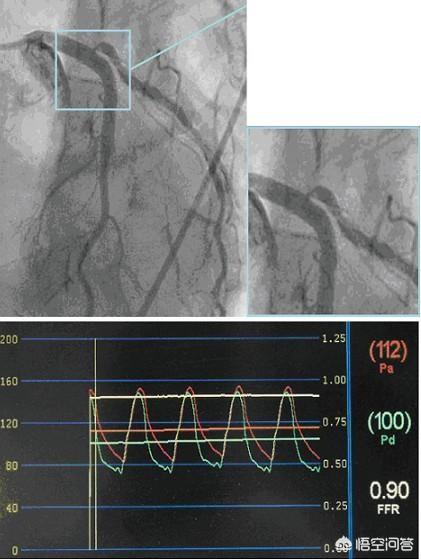

Mais il s'agit là d'un jugement subjectif. Existe-t-il un test objectif capable de fournir une analyse qualitative ? La réponse est oui : la FFR, ou fraction de réserve de flux, est un test plus objectif. Ce test peut mesurer si le vaisseau sténosé est ischémique ou non, plutôt que de se fier à la seule expérience de l'interventionniste ; une FFR > 80 % signifie qu'il n'y a pas d'ischémie myocardique et que la pose d'un stent n'est pas nécessaire ; une FFR < 75 % signifie qu'il y a une ischémie myocardique et que la pose d'un stent est nécessaire.

La pose ou non d'un stent doit donc être combinée aux symptômes cliniques et à la coronarographie. Si l'on n'est toujours pas sûr que la lésion soit ischémique ou non, il est recommandé de procéder à un examen FFR afin d'obtenir des preuves plus objectives.